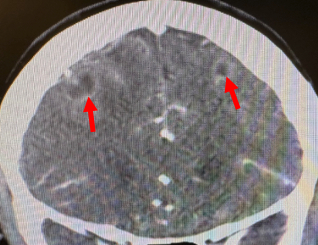

Case: A 65-year-old woman with end-stage renal disease status post renal transplant and on chronic immunosuppression presented with two days of worsening dyspnea. She was hypotensive and tachycardic but afebrile and without leukocytosis. TTE showed a moderate pericardial effusion with early tamponade physiology and a partially mobile 1.8 × 1.0 cm mass attached to the posteromedial papillary muscle, interpreted as tumor or thrombus (Figure 1). Cardiac MRI was recommended but deferred due to instability. CT chest with contrast revealed several pulmonary nodules, two masses in the right breast, and an enlarged mediastinal lymph node—findings suggestive of widespread malignancy (Figure 2). The patient then exhibited altered mental status, prompting a CT scan of the head, which identified ring-enhancing lesions in the brain (Figure 3). Subsequently, samples of blood and pericardial fluid revealed the presence of disseminated Aspergillus fumigatus.